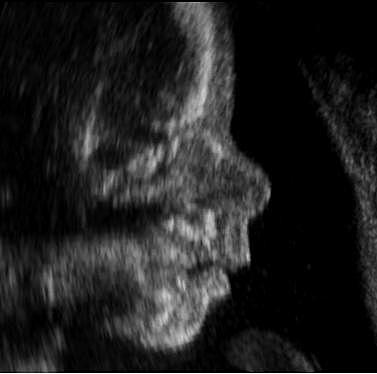

6TO Mes

El feto tiene un rostro bien definido, con pestañas y cejas. hace movimientos mas rápidos y explora su entorno y sus propias extremidades. Identifica sonidos, responde a la música y ya puede abrir los ojos. Luce las proporciones que tendrá al nacer

7MO. Mes

En esta etapa maduran los pulmones y el esqueleto, aumentando notablemente el tamaño del feto, por lo cual presiona la vejiga materna. La activación de melanocitos pigmentan los ojos y la piel. El feto se va posicionando para el parto